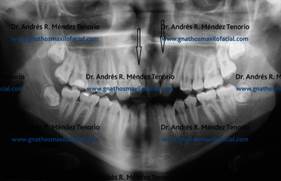

| Radiografías antes y después de las extracciones de dientes supernumerarios | |